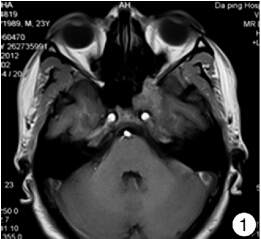

蝶窦粘液囊肿一例

原创蓝十字脑科25岁女子阵发性剧烈头痛缘由罕见蝶窦囊肿

经鼻内镜治疗蝶窦炎性疾病的手术方式和策略

原发性蝶窦结核1例

有一种头痛叫做蝶窦炎症